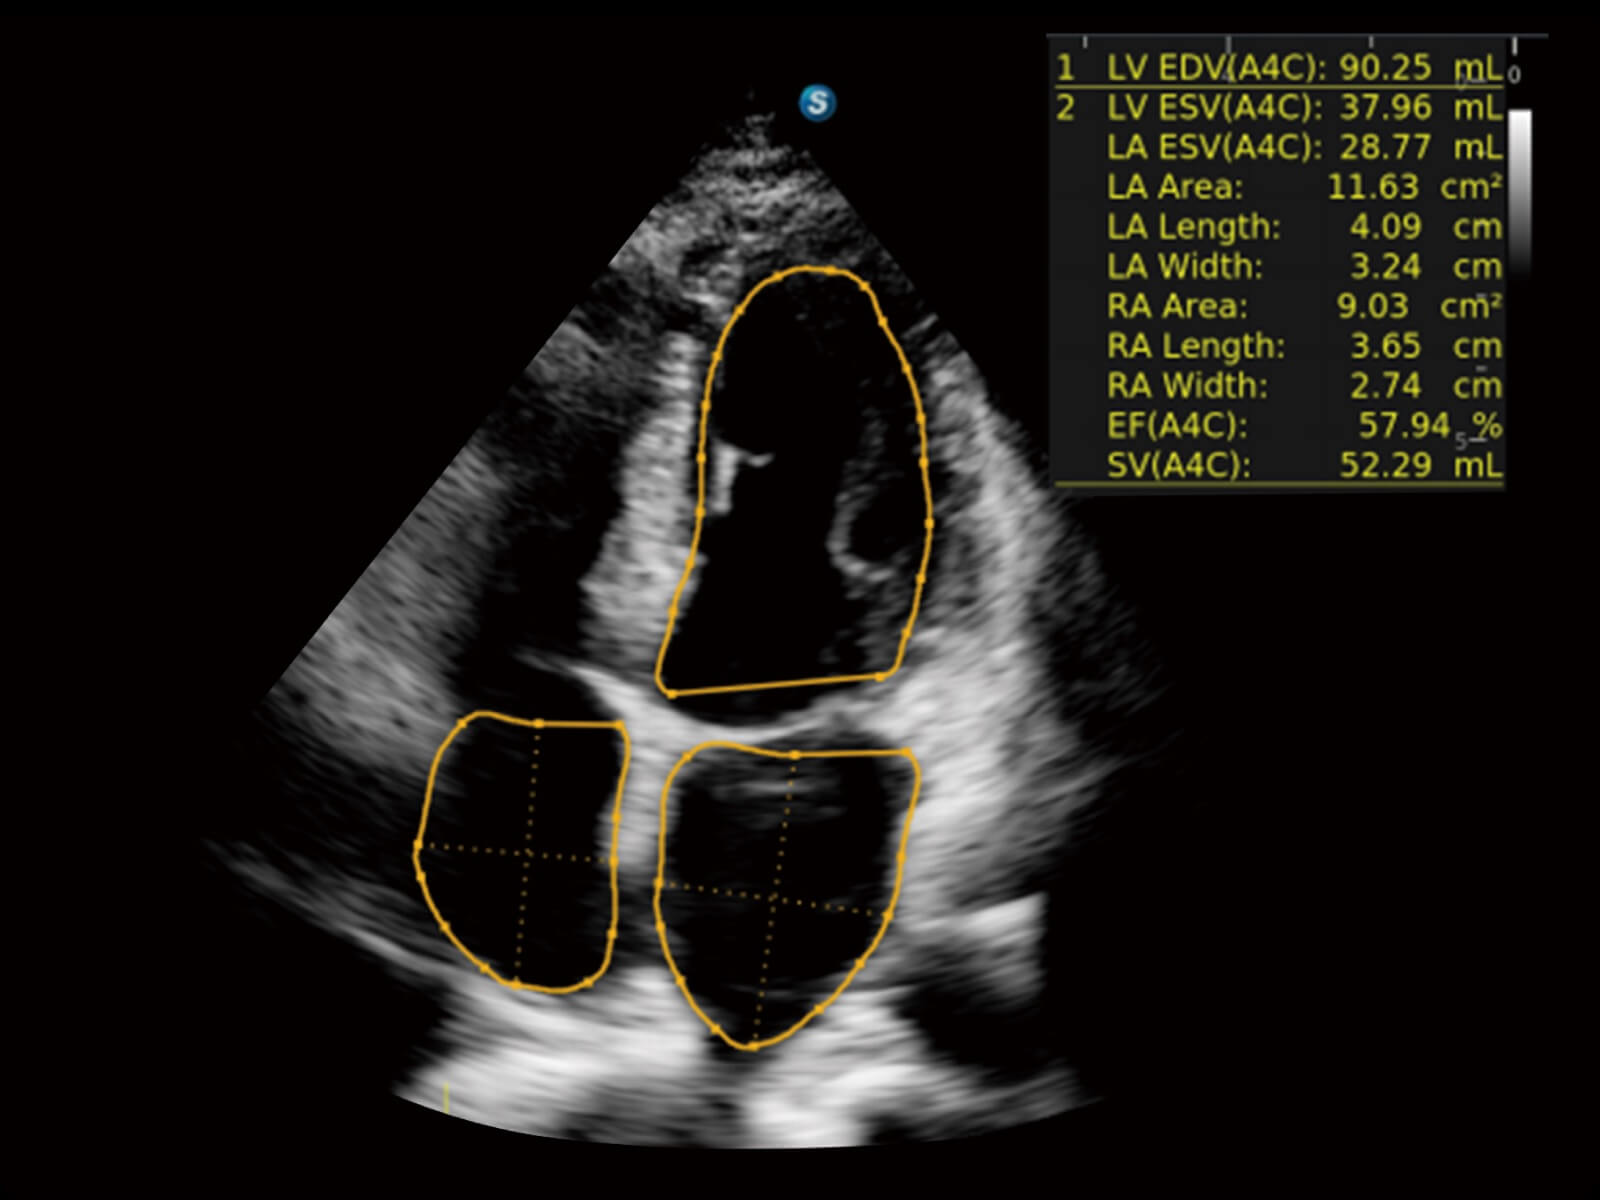

心脏应用

轻松测量